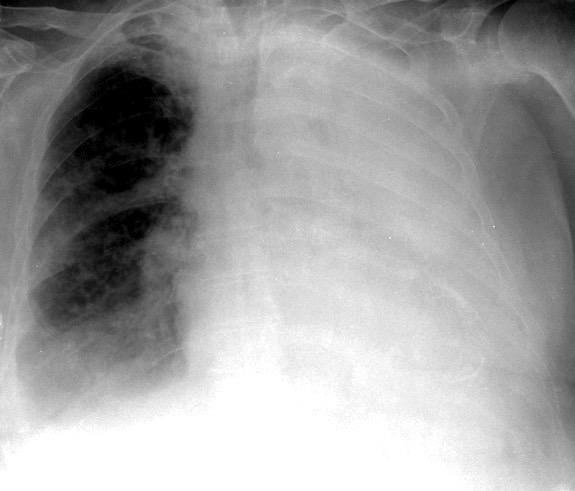

Carcinoma microcítico con síndrome de VCS